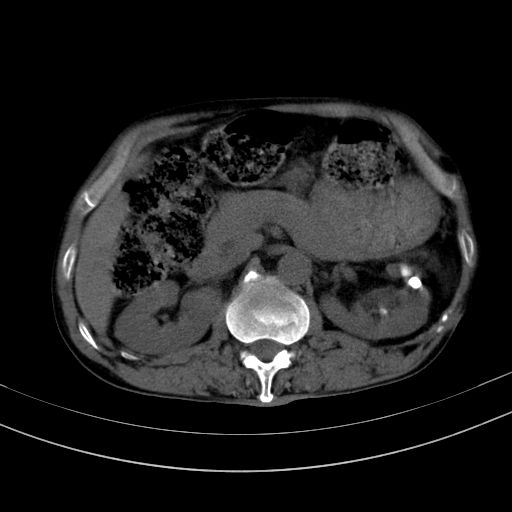

以下是引用dyqct在2010-1-9 17:56:00的发言:[br]考虑:1.双肾囊肿,左肾积水结石、旋转不良。[br] 2.右侧腹直肌血肿或纤维瘤。[br]肠道准备不好。做个增强。